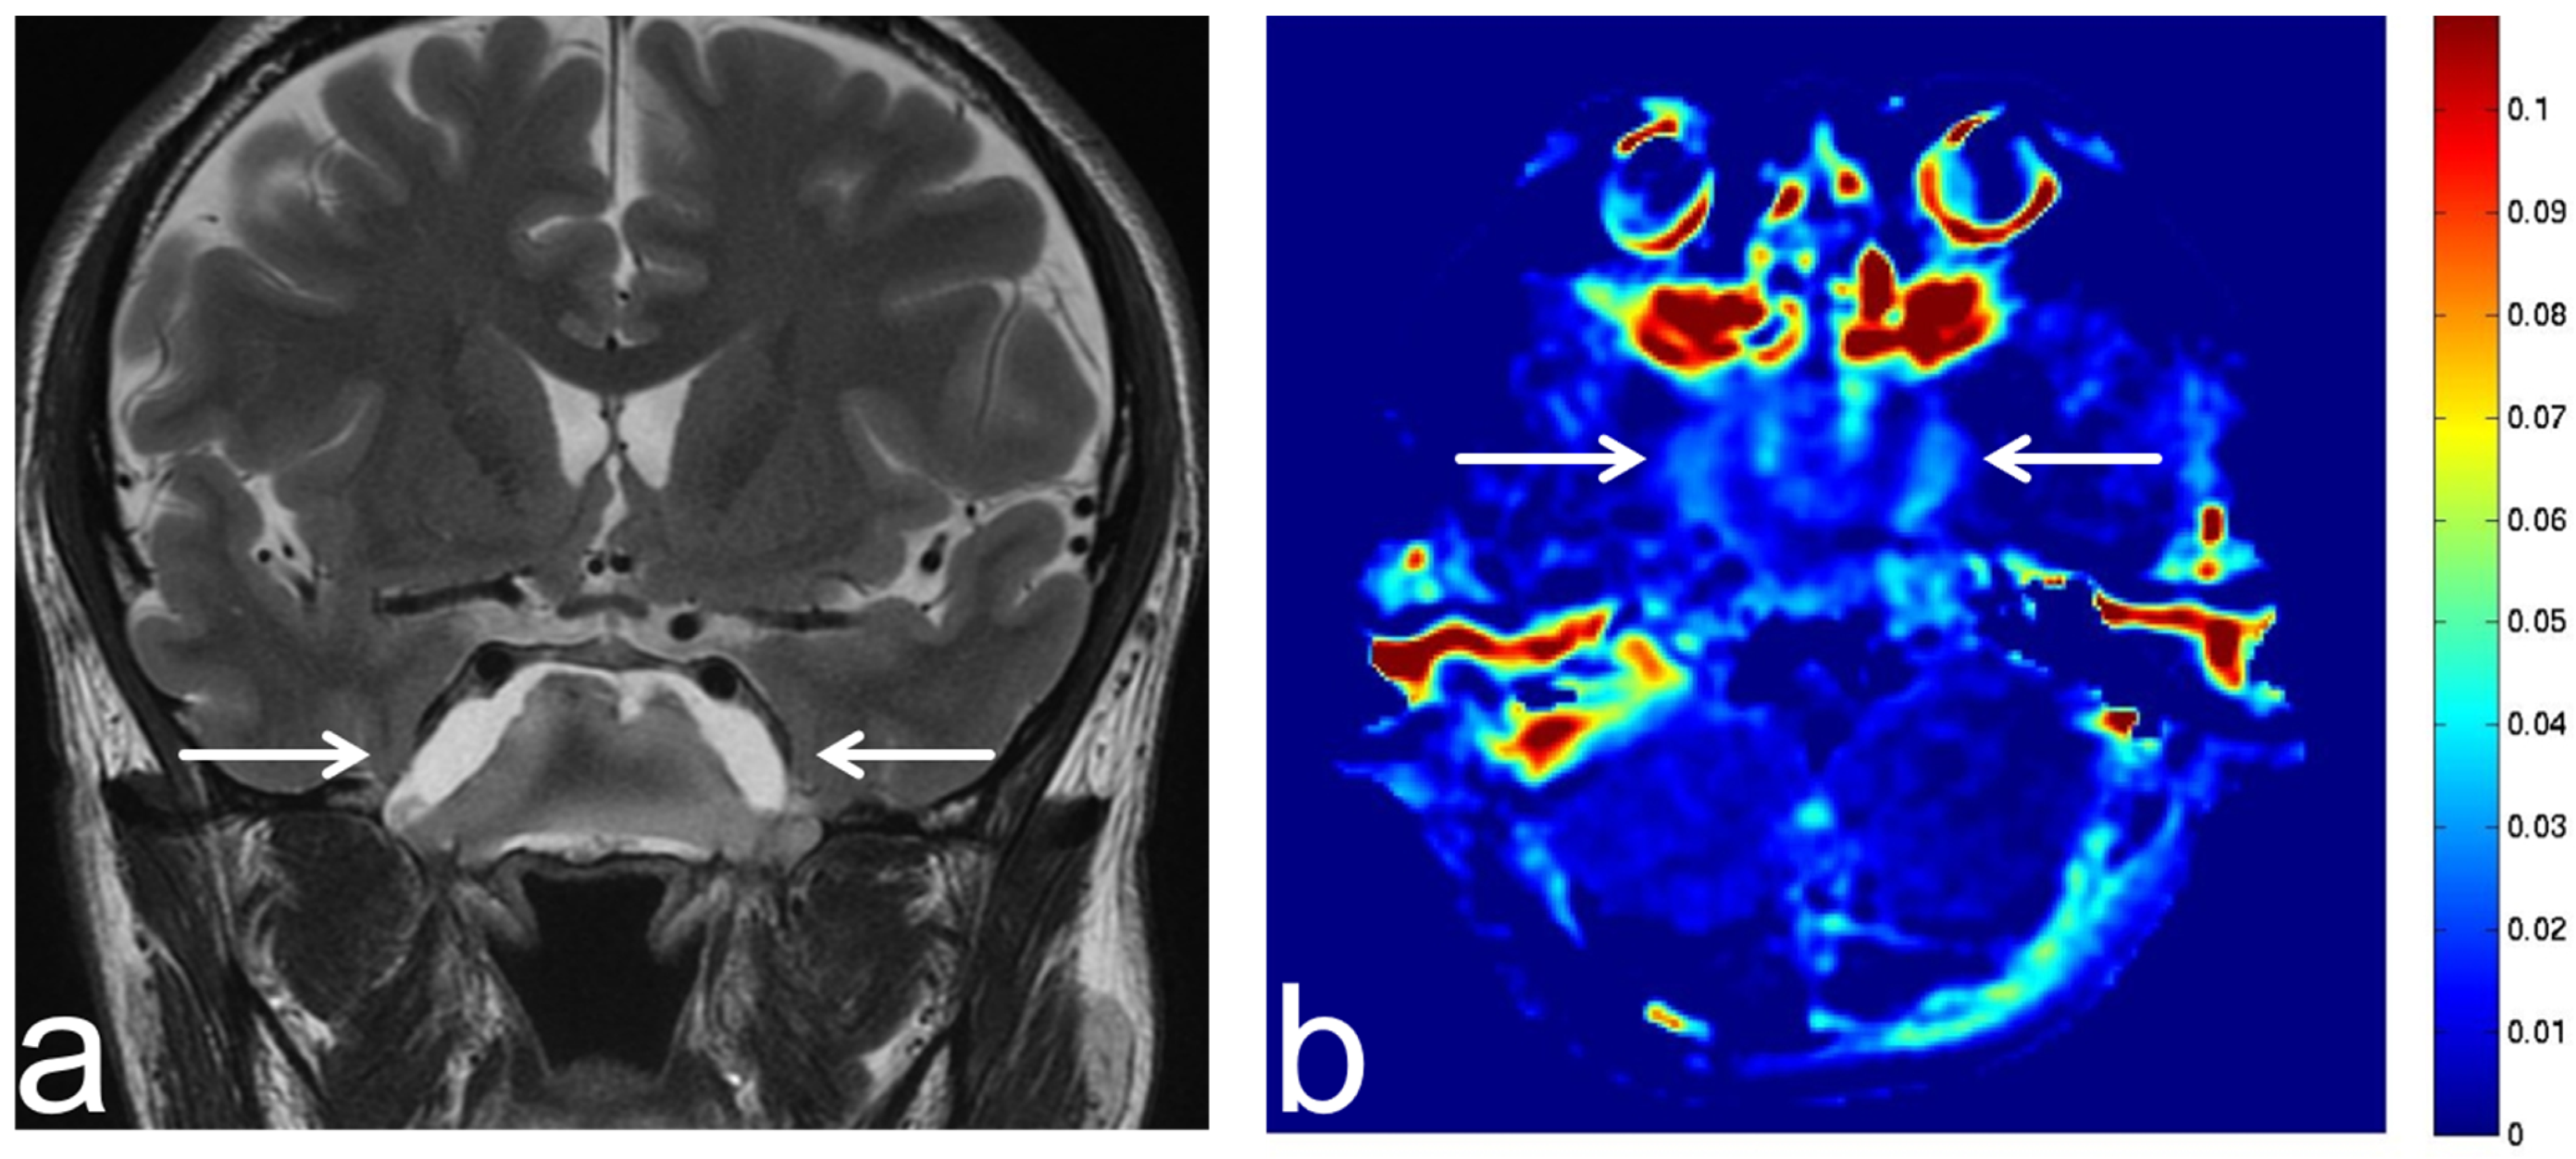

5.1. Oligodendroglioma

5.2. Diffuse Astrocytoma